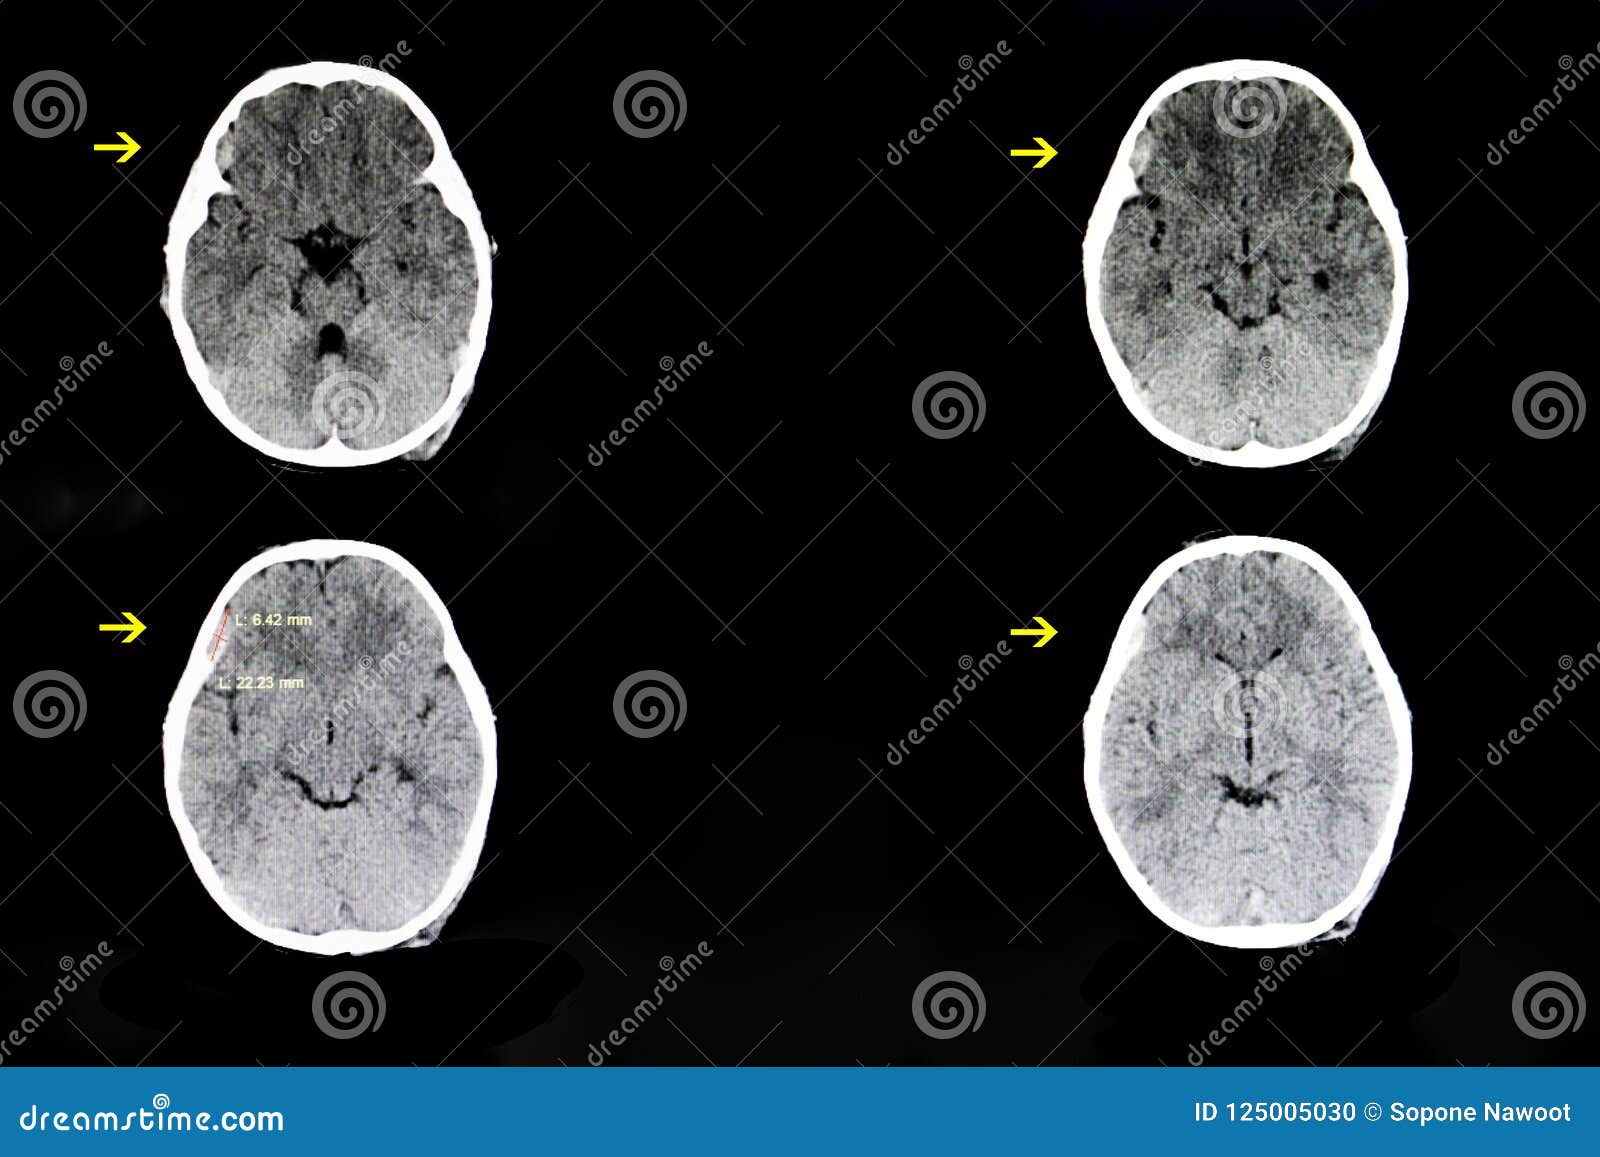

Un ematoma subdurale è una raccolta di coagulazione del sangue che si forma nello spazio subdurale Questo è lo spazio tra due delle meningi, che formano il rivestimento protettivo che copre il cervello. Department of Neurosurgery Subdural Hematoma (SDH) A guide for patients and families 3 Subacute subdural hematomas are ones found within 37 days of an injury Chronic subdural hematomas may take weeks to months to appear These are more commonly seen in the elderly population where brain shrinkage. Ematoma subdurale hematoma usually associated with traumatic brain injury.

Essendo l’ematoma subdurale un’emergenza sanitaria di una certa importanza, per la diagnosi effettiva la risonanza magnetica non è indicata di routine poiché presenta dei tempi di esecuzione nettamente maggiori rispetto alla tomografia computerizzata e non è accessibile a tutti i pazienti (quali ad esempio persone portatrici di pacemaker). Walter Krauland, Walter Krauland, Verletzungen der kortikalen Schlagadern, subdurale Blutung, Verletzungen der intrakraniellen Schlagadern, /, (), (19) Crossref A Norman Guthkelch, The Aetiology and Evolution of Chronic Subdural Haematoma, Topical Reviews in Neurosurgery, /B. Chronic subdural hematoma A chronic subdural hematoma (SDH) is a collection of blood on the brain’s surface, under the outer covering of the brain () It usually begins forming several days or.

While bleeding during pregnancy may be a sign of miscarriage, another possibility is a subchorionic hematoma, which is often more manageable. Ematoma subdurale cronico dell’adulto EMC Neurologia, Vol 17, No 4 Age determination of subdural hematomas with CT and MRI A systematic review European Journal of Radiology, Vol , No 7 Subacute and chronic subdural hematoma in young population less than 40 years. Evacuation of a right sided hyperacute subdural hematoma (SDH) 2 consecutive Head CT scans showed enlargement of the clot over 1 hour Active arterial blee.